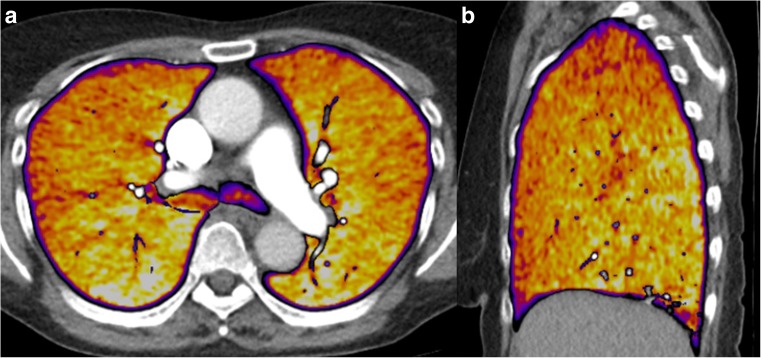

The subtraction software automatically selects the unenhanced and enhanced scans, applies a mask to extract only the lung areas and registers and deforms the lungs in the unenhanced scan to their shape and position in the enhanced scan. After subtraction, it automatically generates 1-mm greyscale iodine maps of the lungs with exclusion of the large vessels and 5-mm heat scale colour maps as an overlay on top of the CTPA images. These maps reflect true Hounsfield unit density differences in the pulmonary parenchyma between the two scans, with a pre-set WW/WL of 100/50 (Fig. 2). It is possible to reconstruct afterwards images at their own preference thickness, for example, even thicker slices, like 10 mm.

Fig. 2.

5-mm (a) axial and (b) sagittal reconstructions of a subtraction iodine map on top of CTPA of normally-perfused lungs in a supine position. Both reconstructions show a normal gravity-dependent gradient, in the ventro-dorsal and the cranio-caudal direction